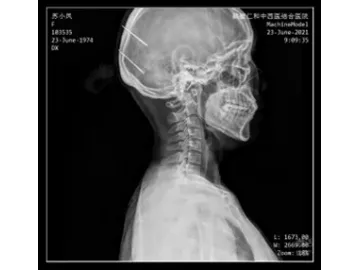

- Herramientas de navegación: El visor de imágenes integrado en el equipo cuenta con un conjunto completo de herramientas diseñadas para facilitar la revisión y el análisis clínico. Incluye funciones como zoom, rotación de imagen (90° a la izquierda o derecha), volteo horizontal y vertical, acercamiento, alejamiento y opción para volver al tamaño original. También permite mover la imagen libremente en pantalla, invertir los colores, ajustar el tamaño de forma automática y seleccionar una región de interés (ROI) para análisis detallados. Otras funciones avanzadas incluyen lupa de aumento localizado, ajustes de ancho y nivel de ventana predeterminados o personalizados dentro del ROI, visualización de valores de gris en puntos específicos, procesamiento de imagen mejorado y mediciones de escala de grises en áreas elípticas.

- Herramientas de medición: Haz mediciones rápidas y precisas con funciones como flechas para señalización, cálculo del índice cardiotorácico (CTR), medición de distancias y ángulos, así como evaluación de la alineación en la columna vertebral. Todo al alcance de un clic, para facilitar los diagnósticos.

- Su tecnología de vanguardia garantiza imágenes nítidas, sin distorsiones y con una resolución excepcional, lo que mejora notablemente la precisión diagnóstica.

- Permite capturar imágenes puntuales en milisegundos durante la visualización o reproducción de los estudios. Esto brinda a los profesionales la posibilidad de detectar áreas sospechosas con mayor certeza, reducir errores de diagnóstico y acelerar la elaboración de informes.